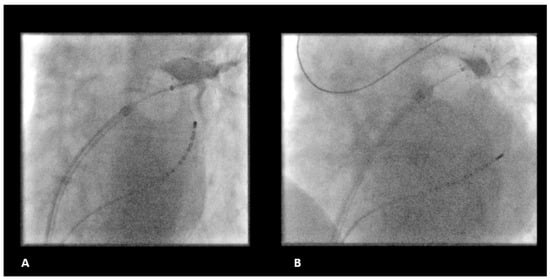

:1. Introduction

2.2. Ablation Procedure